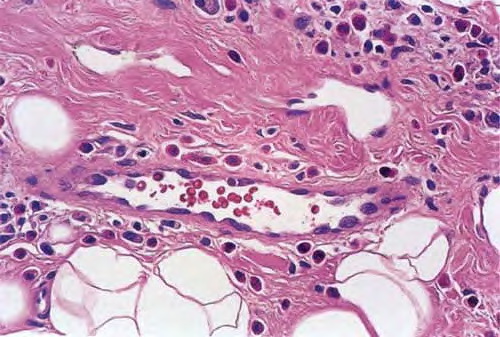

It is possible that Kimura disease represents a florid, subcutaneously deep-seated form of the same basic pathogenetic process that gives rise to classic dermal CLH. There is controversy regarding whether Kimura disease and ALHE are variants of the same disorder, although most favor the concept that they are distinct clinicopathologic entities despite some clinicopathologic overlap. The terms epithelioid hemangioma and pseudopyogenic granuloma have been used as synonyms for ALHE. Some regard ALHE essentially as a malformation of blood vessels caused by an underlying arteriovenous shunt. They consider the CLH-like aspects of the lesional infiltrate to be a secondary feature. Those who believe that ALHE should be classified as a separate disorder argue that, compared with the lesions of Kimura disease, ALHE lesions tend to be smaller  and more superficial (centered in the dermis rather than the subcutis) and exhibit a more prominent vascular hyperplasia, characterized by small blood vessels lined by plump endothelial cells with abundant cytoplasm and sometimes atypical nuclei . In addition, there is often evidence of arteriovenous anastomoses, the lymphoid infiltrate is less extensive, secondary lymphoid follicles are present in only a minority of cases, and lymphadenopathy is usually absent. Patients with both AHLE and Kimura disease have been shown to harbor dominant clonal T-cell populations in some cases.

Histopathologically, the dermis and/or subcutis exhibit hyperplasia of small blood vessels lined by plump endothelial cells similar to those present in the high endothelial venules of lymphoid tissues. These venules are a major point of lymphocyte trafficking between the blood and the paracortical T-cell domain of lymph nodes. Surrounding these hyperplastic vessels is a dense infiltrate composed of small lymphocytes, plasma cells, histiocytes, and eosinophils. The latter are typically prominent but may be absent in some cases. There are usually multiple secondary lymphoid follicles with prominent germinal centers, particularly in the subcutaneous lesions. In general, lesions are more superficial and the vascular features are more prominent in AHLE, whereas lesions are deeper and the lymphoid features are more prominent in Kimura disease.